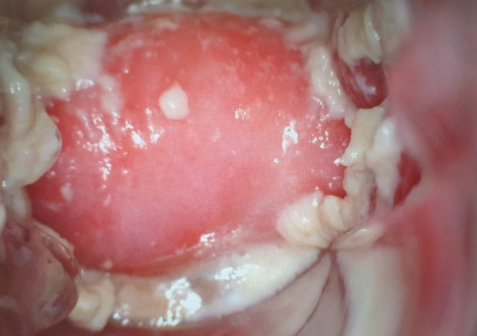

반응성 세포변화란 세포가 염증, 감염, 자극 등의 원인에 반응하여 일시적으로 변형된 상태를 말합니다. 이는 자궁경부세포검사(Pap smear)에서 흔히 나타나는 결과 중 하나이며, 대부분은 양성(비암성)입니다.

자궁경부세포검사에서 발견되는 반응성 세포변화는 자궁경부에 생긴 염증이나 감염, 호르몬 변화 등의 반응으로 세포의 형태나 배치에 약간의 변형이 생겼다는 의미일 뿐, 곧바로 자궁경부암을 의미하는 것은 아닙니다.

반응성 세포변화 염증소견은 염증 반응이 관찰되면서 세포의 모양이 일시적으로 변한 경우입니다. 이 경우 대개는 세균성 질염, 칸디다, 트리코모나스 등의 감염이 원인이며, 항생제 치료만으로 회복될 수 있습니다.

하지만 반복적으로 반응성 세포변화 염증소견이 발견되거나, 염증이 오래 지속될 경우, 자궁경부에 만성적인 손상을 줄 수 있고 이로 인해 정밀 검사가 필요할 수도 있습니다.